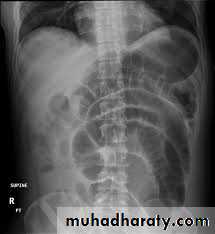

Appendicitis

Appendicitis may occur during pregnancy but is more common immediately postpartum. Because the appendix rises in the abdomen as pregnancy progresses, pain and tenderness may not occur in the classic right lower quadrant location, and pain may be mild and cramping, mimicking pregnancy-related symptoms. Also, WBC count is normally somewhat elevated during pregnancy, making WBC count even less useful than usual. Serial clinical assessment and compression-graded ultrasonography are useful.Because diagnosis is often delayed, mortality rate from ruptured appendix is increased during pregnancy and particularly postpartum. Thus, if appendicitis is suspected, surgical evaluation (laparoscopy or laparotomy depending on the stage of pregnancy) should proceed without delay.